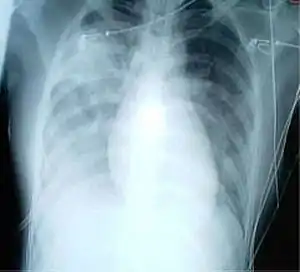

Radiologie

L’imagerie radiologique occupe une place importante dans le diagnostic initial de syndrome respiratoire aigu sévère puis dans le suivi de l’efficacité du traitement. Les images les plus typiques comportent une localisation périphérique prédominante, des opacités alvéolaires unilatérales et focales progressant sous traitement vers une atteinte unilatérale multifocale ou bilatérale. Il n’existe ni excavation, ni adénopathie, ni épanchement pleural. Le scanner thoracique est un examen complémentaire qui permet en général de préciser les signes de pneumopathie sévère.